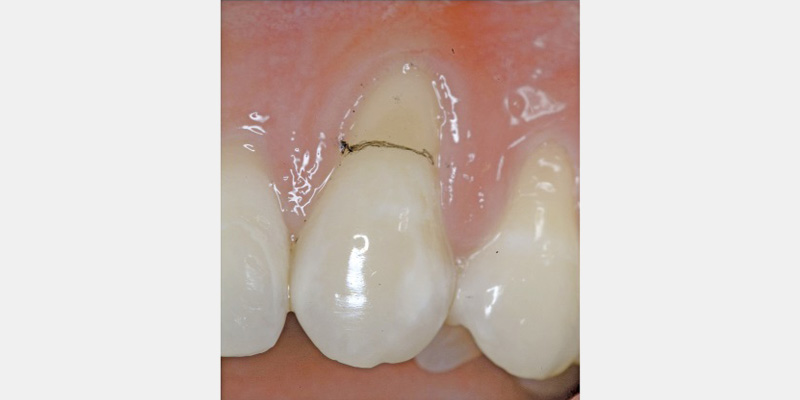

Histologic evidence from a recent study shows that regeneration can be achieved with rhPDGF-BB, β-TCP, and collagen in gingival recession-type defects.12 Gingival recession defects have been treated successfully with rhPDGF, β-TCP and a collagen membrane with a root coverage technique (Figures 6–7). This technique was compared to a subepithelial connective tissue graft within a case series,13 and more recently in a controlled clinical trial. The comparisons demonstrated that the growth factor technique was comparable to the others for root coverage outcomes.14 Many studies validate the use of EMD for periodontal and mucogingival defects.5, 6, 15 The histological article on EMD offers proof of principle for incredible quantities of true periodontal regeneration.16

Results showed the injection of autologous fibroblasts created significant improvement when compared to a placebo. Prior to the injection of these expanded fibroblasts, a “priming” procedure was performed in the papillary region to create an inflammatory response. The theory was to develop temporary increased tissue volume by causing inflammation, thus enabling the injection of more volume of the concentrated cell suspension. The cells were delivered 5-7 days after the priming procedure and then again at two other times following the first injection. The subjects were assessed at two, three and four months after the injections. Preliminary results indicate a novel tissue-engineering technique may hold promise in resolving the challenging open interproximal space.21 Further research is under way to evaluate this as a predictable therapy (Figs. 4A-4B).